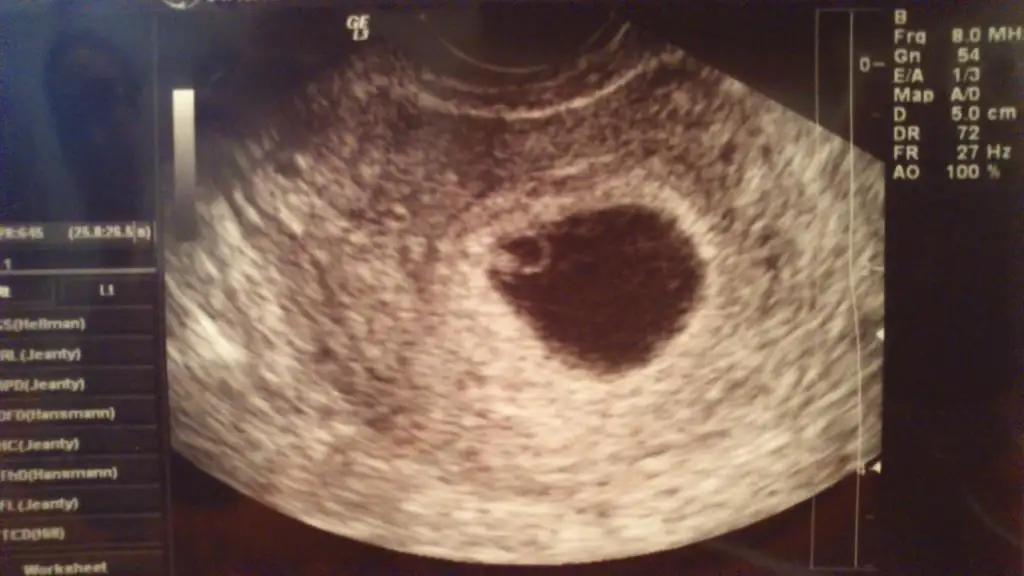

Bu da benim ultrason çıktım, bu damla gibi, 2 resim daha vardı onlar da fasulye tanesi gibi :) benim içime de erkek doğuyor bakalım ne çıkacak.

bu arada senin bızdık erkek gibi kesen damlaya benziyor dimi tatlım:1: